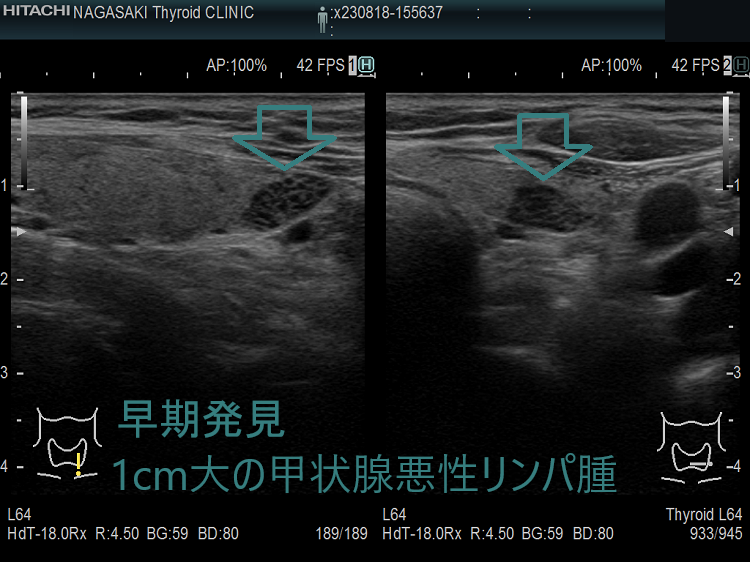

以下は長崎甲状腺クリニック(大阪)にて偶然から見つかった33歳男性の甲状腺悪性リンパ腫(命に係わる甲状腺癌)症例です。早期発見だったため、甲状腺全摘手術で完治し、5年以上経った今も長崎甲状腺クリニック(大阪)に通院されています。

もともと、奥さんの甲状腺機能低下症/橋本病を長崎甲状腺クリニック(大阪)で治療中。「一度、主人も診てやってください」の一言から、特に甲状腺の病気を疑うわけでないのに血液検査と甲状腺超音波エコー検査をおこなったところ甲状腺機能正常橋本病でした。この時(32歳時)は甲状腺悪性リンパ腫を疑う所見はなく、1年後の再診を指示しましたが、来院されたのは1年10か月後。 橋本病は甲状腺癌の発生母体であるため、当然のごとく甲状腺超音波エコー検査を施行。

(写真参照)右葉中部に18.5 x 13.2 x 8.8 mmの甲状腺悪性リンパ腫を認め、大阪市立大学(現、大阪公立大学) 内分泌外科(現在は業務統合のため廃止)にて根治的甲状腺全摘手術をおこない完治。発見が早かったため甲状腺から外に出ておらず、術後の抗がん剤も一切必要なく経過。5年以上経った今も元気に御夫婦で来院されています。もしも、甲状腺超音波エコー検査を行っていなければ、命を失っていた可能性大です。